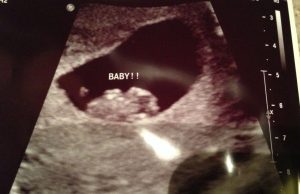

Are you pregnant and curious about your baby’s sex? Don’t worry, you’ll be able to find that out after the first ultrasound.

This method takes into account the location of the placenta during the first ultrasound performed in the initial gestational period.

Although limbs start to develop after the fourth week of gestation, the Ramzi method allows the determination of the baby’s sex through the study of images before 8 weeks of gestation.

How did he do it? First of all, he started by analyzing the bright area around the gestational sac where the placenta begins to grow.

During the early stages the baby stays very close to the placenta. The most important thing to do is look for the bright area.

Search for the images from your first ultrasound and take the following tips into consideration:

- In the case that you find your first vaginal ultrasound; if the fetus is implanted on your left, it is a girl. In the case the fetus is found on the right then it will be a boy.

- If you find an abdominal ultrasound, the results should be read as a mirror imagine. Therefore, if you see that the placenta is on the right (it means it is actually on the left) you should expect a little girl. If you find the placenta on the left (it means it is on the right) it’s time to prepare for your little boy.

If you find it difficult to interpret the ultrasound or to find the placenta, don’t worry, simply ask your doctor.